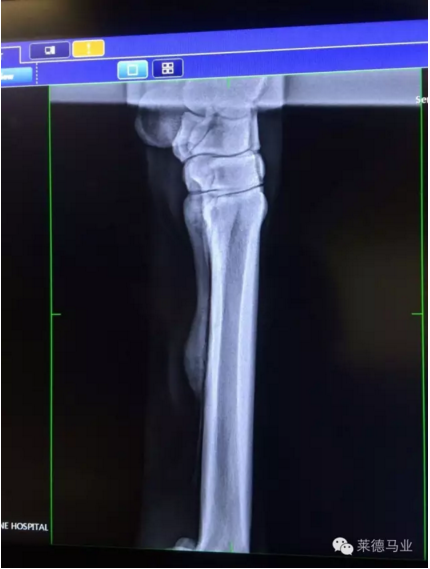

数码X光机

X光片